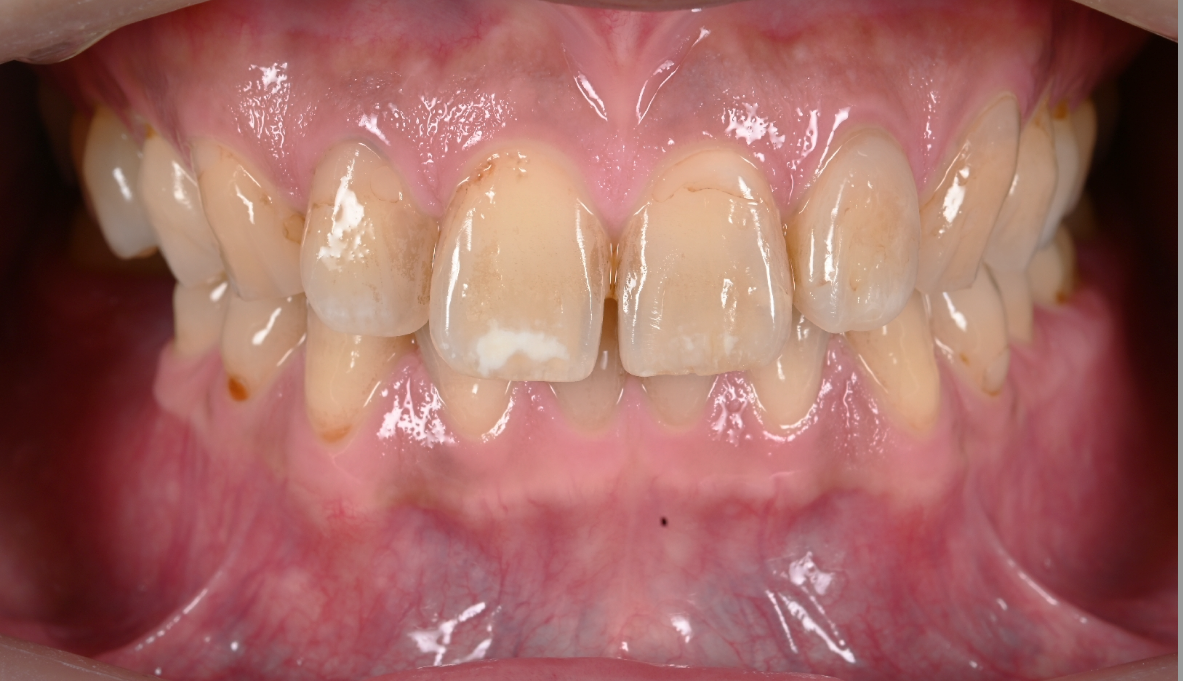

今回ご紹介する患者様は、前歯の白い模様(ホワイトスポット)が気になるということで来院されました。

また、ホワイトニングにもご興味があるということだったのでアイコン治療を始める前にホワイトニングもされ、前歯だけではなく全ての歯を白くきれいに改善されてます!

Before